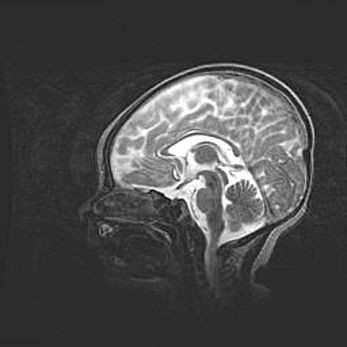

Аномалия Денди-Уокера. Признаки гипоплазии мозолистого тела.

Возраст: 5 месяцев 3 дня

Вес: 5550 г

Пол: мужской

Окружность головы: 39 см

Срок гестации: 40 недель

Аномалия Денди-Уокера – это порок развития головного мозга, для которого характерна триада симптомов: гипотрофия или аплазия червя мозжечка и/или полушарий мозжечка, расширение четвёртого желудочка с формированием ликворной кисты задней черепной ямки, гипертензионная гидроцефалия различной степени.

Гипоплазия мозолистого тела относится к дефектам внутриутробного этапа развития мозговой ткани, возникающим в процессе закладки структур головного мозга, что происходит на начальных этапах развития эмбриона.